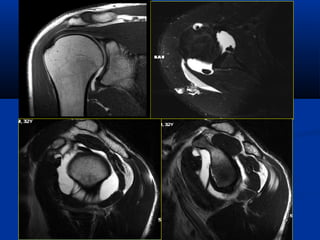

MRI – C ng h ng tộ ưở ừ